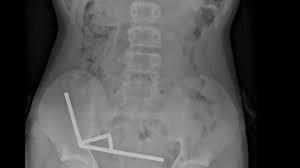

Die Magneten, die in Neuseeland seit Anfang 2013 verboten seien, seien auf der Temu-Plattform gekauft worden, teilten die Ärzte mit. Eine Röntgenaufnahme habe gezeigt, dass die Magneten sich in verschiedenen Bereichen des Darms aufgrund der Anziehungskraft zu vier geraden Linien zusammenklumpten. Den Ärzten zufolge starb durch die Kraft der Magneten an vier Stellen im Dünn- und Dickdarm Gewebe ab.